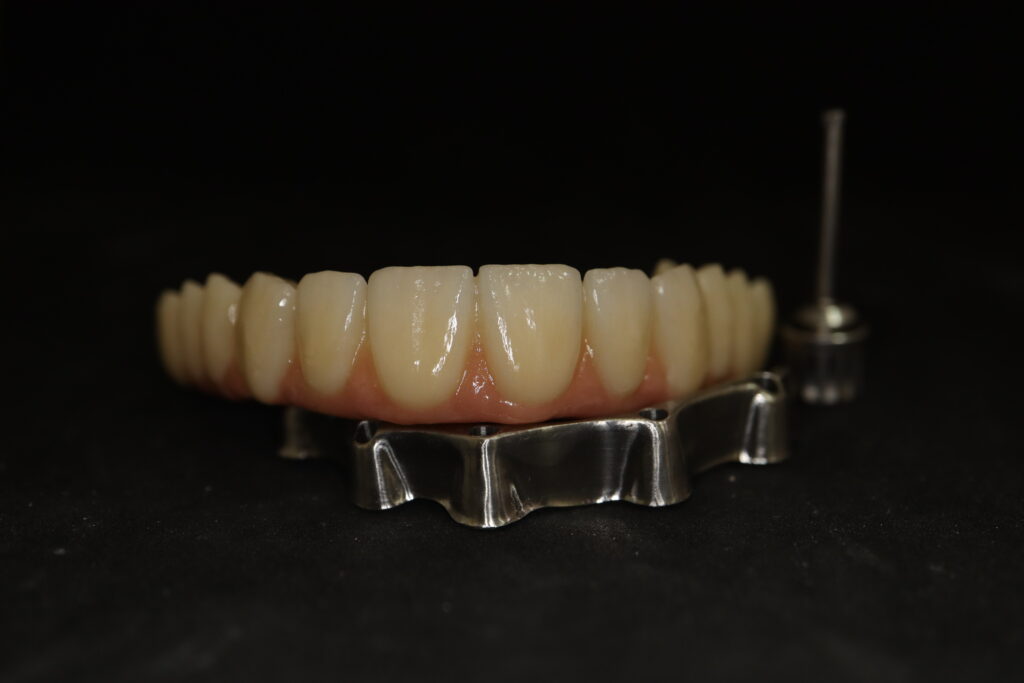

На консультации было принято решение о перепротезировании протезом из диоксида циркония на титановой балке.

Спустя 27 дней был зафиксирован протез с опопрой на дентальные имплантаты из диоксида циркония с каркасом из титана.